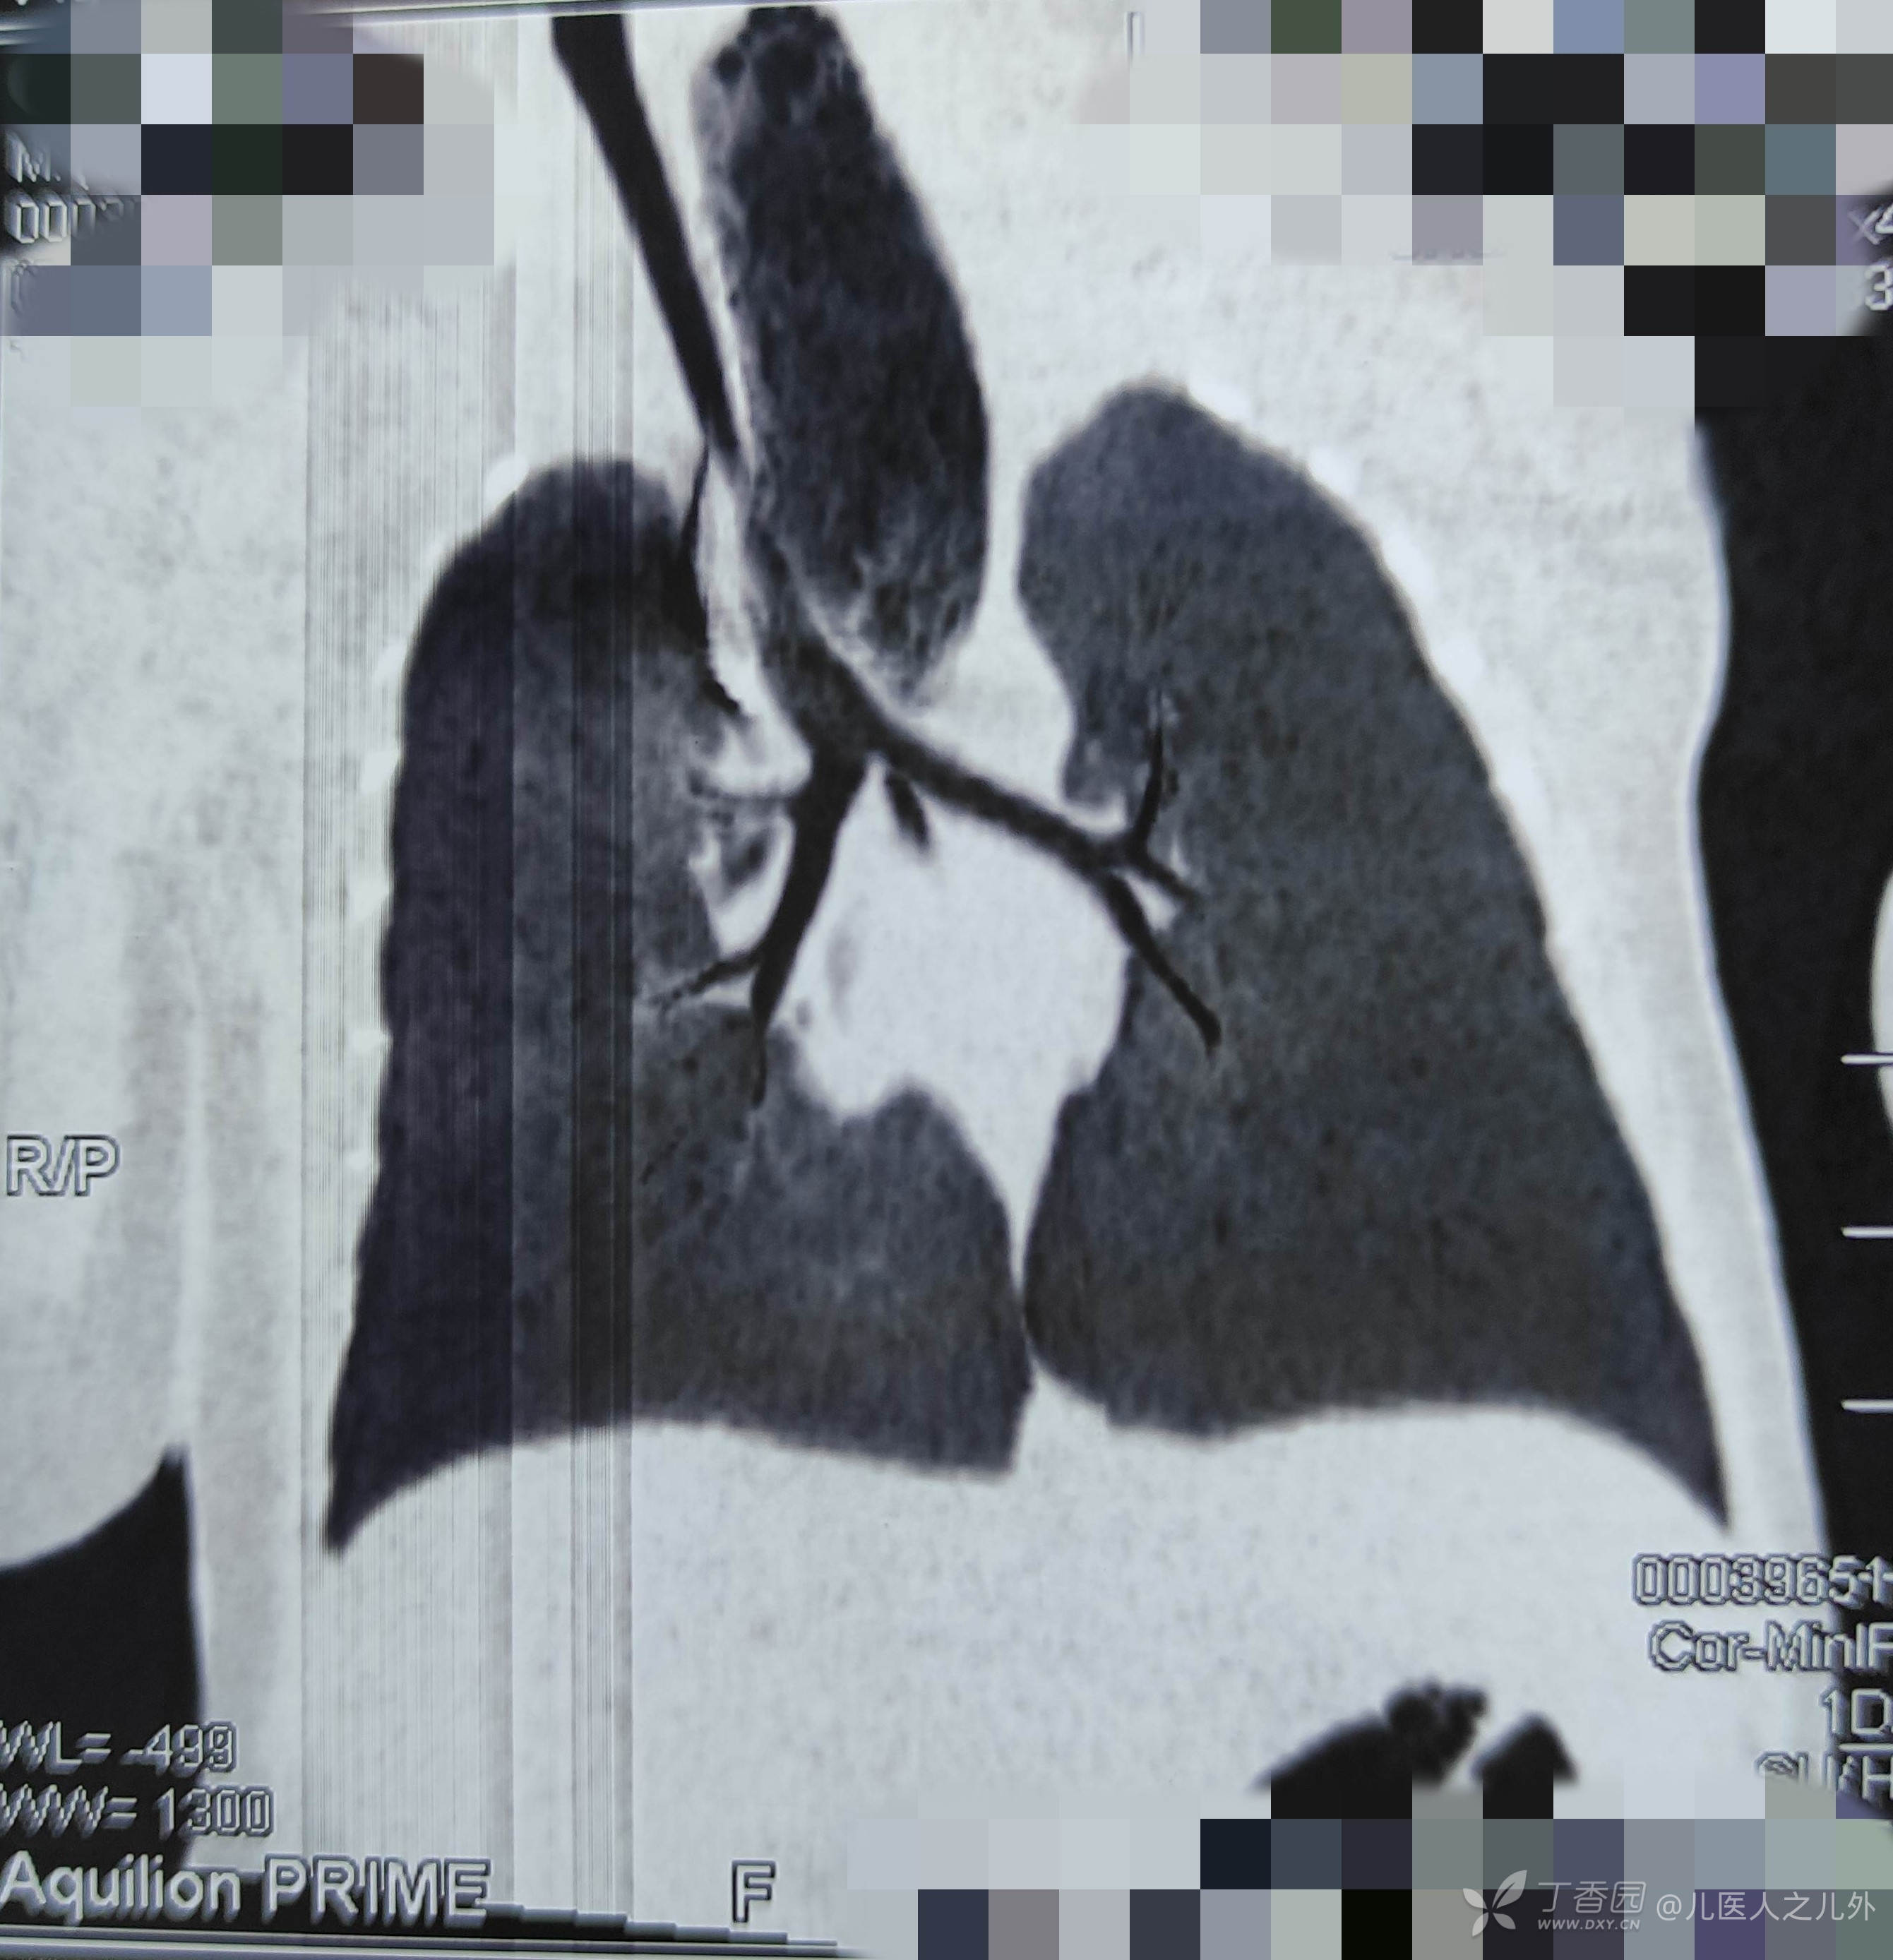

CT胸部纵切面如图,还有未排出的造影剂,可明确食管上盲端与肺的位置关系。可直观看到上盲端端口与气管分叉基本为同一位置。可指导术中上盲端的游离。

CT横切面可看到上盲端,由于宝宝为平卧位,可看到由于造影出现的“气液平”。

上图红标位置,正好为上盲端及气管食管漏分叉的位置,可见上下盲段“联系紧密”,临床病理分型为IIIb型。